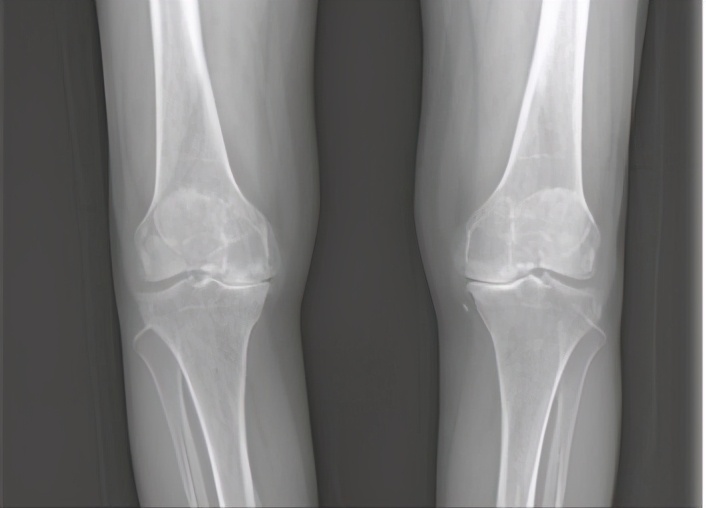

正常的髌股关节

饱经沧桑的髌股关节